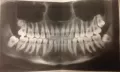

Здравствуйте! Полтора года назад почувствовала в левой челюсти дискомфорт (тянущая боль, не зависящая от внешних воздействий), отдавало в шею и ухо. В семерке обнаружился неглубокий кариес, но после лечения ощущения не исчезли. Спустя время дискомфорт начал усиливаться: боли нет, но челюсть распирает, а вокруг шестерки и пятерки десна припухла. Сделала панорманый снимок — а там четко под ними остатки пломбировочного материала (ему более 3 лет) + зуб мудрости давит на нерв.

Прикрепленые фото

1. Если речь о нижней челюсти, то действительно на верхушках имеется инородный материал, который граничит с нижним каналом.

2. Восьмерка нижняя не давит никуда, но может приносить дискомфорт. Описанные беспокойства (кроме шишки между нижними 5 и 6 зубом), могут быть от этой восьмерки.

3. Также большая проблема у антагонистов, то есть на этой же области, только на верхней челюсти.

4. 28 зуб необходимо срочно удалять, он может быть причиной ваших беспокойств, несмотря на то, что он на верхней челюсти.

5. Также необходимо перелечить 25 зуб и депульпиповать 26, так как пломба стоит на пульпе.